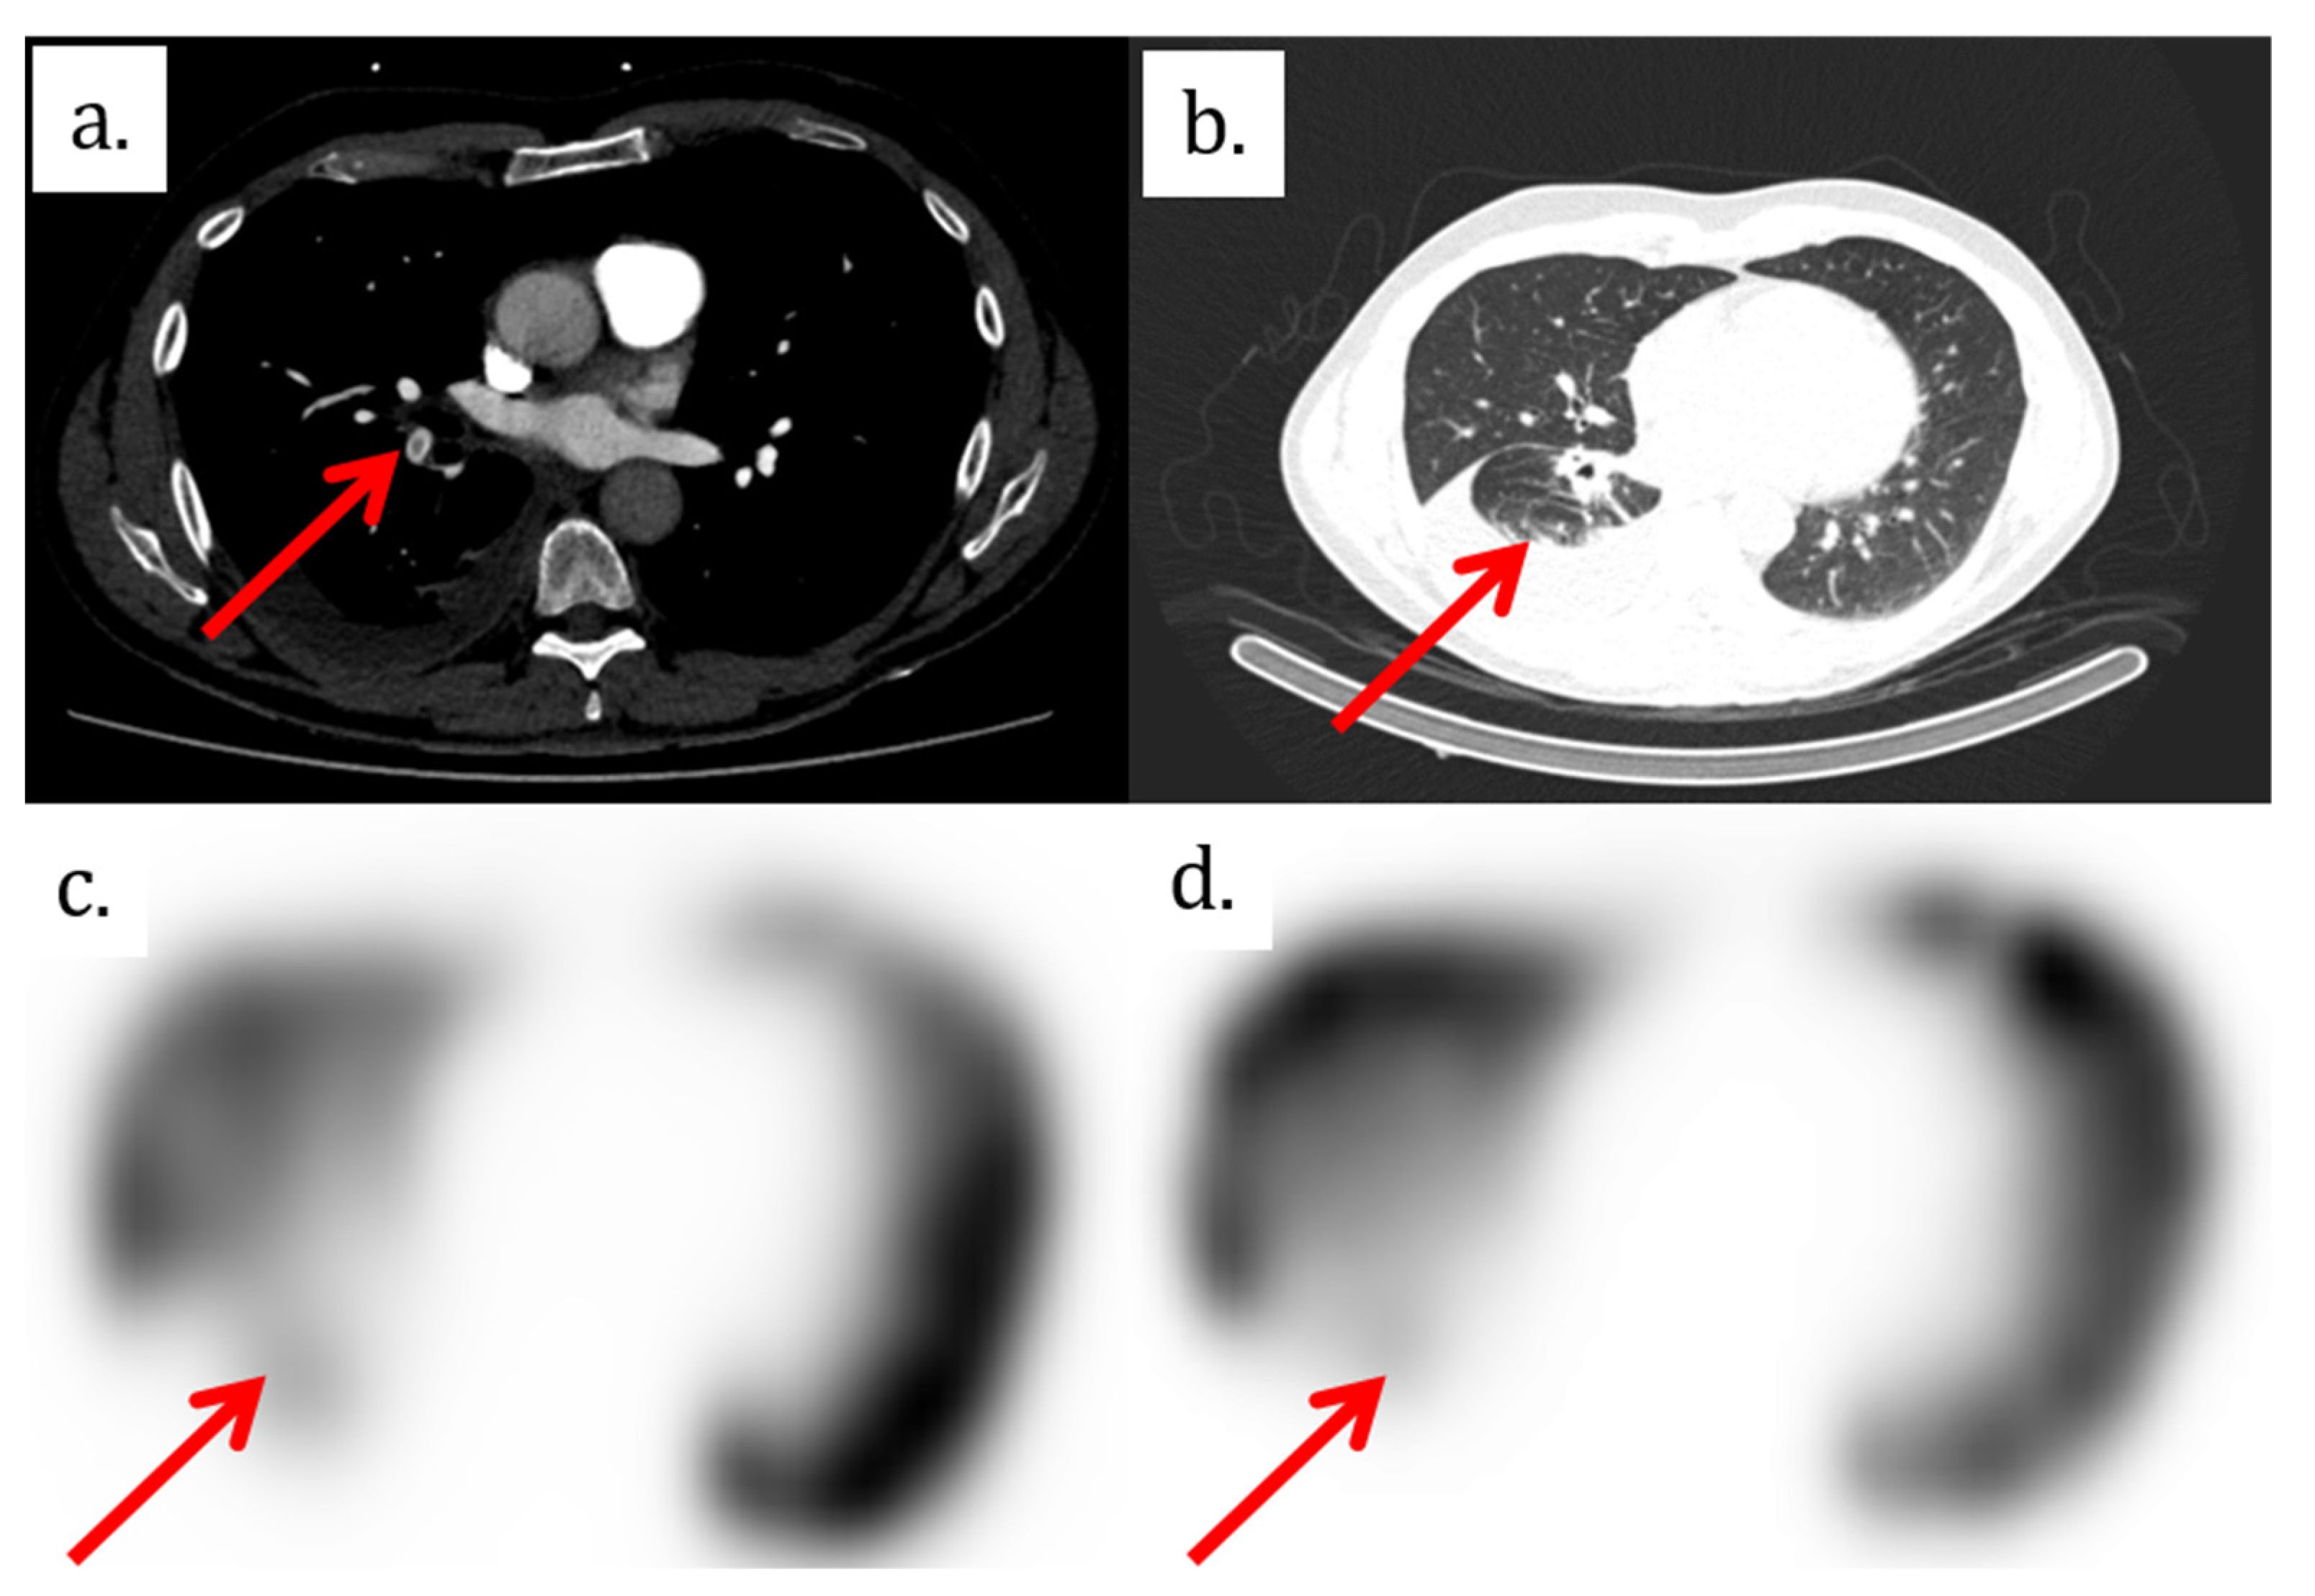

2. Case Presentation